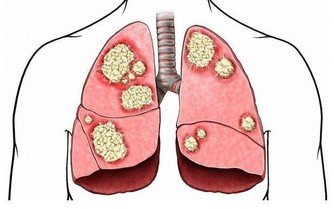

免疫力——抗衰、抗癌的終極武器

現代醫學界發現,免疫力與衰老有密切關係,免疫力減退是導致衰老的因素之一。並且,醫學界還越來越傾向於,提高免疫力能夠抑制腫瘤發生,預防腫瘤復發和轉移,對於癌症患者有重大意義。

可見,免疫力的作用是很強大的。那麼免疫力究竟是什麼?

實際上,我們常說的免疫力,是對免疫系統功能的通俗說法。

而免疫系統,是人體自身的防禦機制,它最大的作用在於識別和消滅外來入侵的異物(包括病毒、細菌等),同時處理衰老、損傷等自身細胞(包括受感染或癌變的細胞),從而保護人們遠離疾病,讓人們保持年輕。